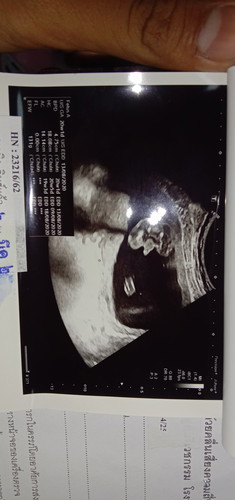

แบบนี้น้ำหนักน้อยกรือตามเกณฑ์ค่ะพอดีไม่ได้ถามคุณหมอค่ะละถ้าน้อยกว่าเกณฑ์ต้องบำรุงยังไงค่ะ